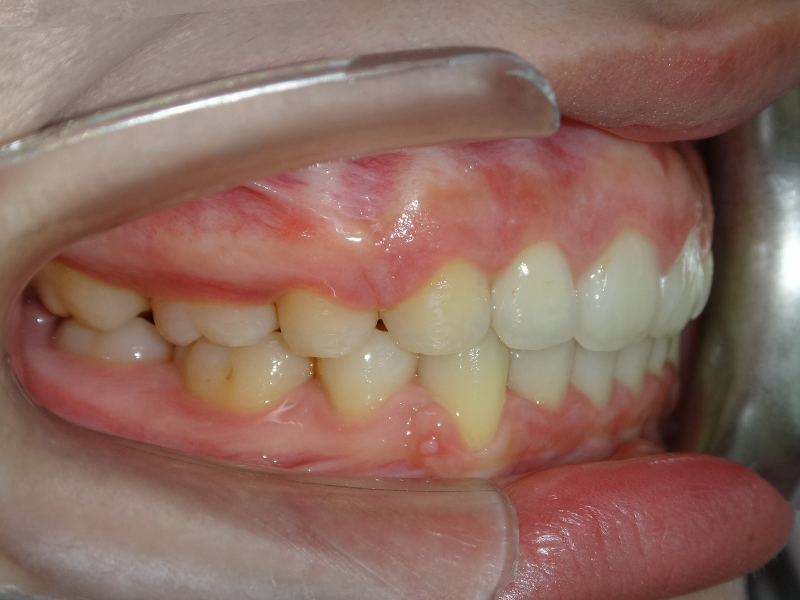

隱適美拔牙改臉型(二) 首頁 案例分享 齒顎矯正 隱適美拔牙改臉型(二) 拔牙改臉型案例 年紀:20 歲 女性 治療方式:隱適美隱形矯正 時間:29個月 主訴:外觀看起來比較暴,希望可以把牙齒排列整齊以及後縮 矯正前 矯正後 矯正前 矯正後 矯正前 矯正後 聲明:本所療程皆由專業醫生評估後,依照個人口腔狀況進行治療。因每位患者個別狀況不同,術後狀況也不盡相同,需親來本所由醫生評估。